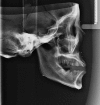

Objectives: The purposes of the study are to investigate the consistency of linear measurements between CBCT orthogonally synthesized cephalograms and conventional cephalograms and to evaluate the influence of different magnifications on these comparisons based on a simulation algorithm.

Methods: Conventional cephalograms and CBCT scans were taken on 12 dry skulls with spherical metal markers. Orthogonally synthesized cephalograms were created from CBCT data. Linear parameters on both cephalograms were measured via Photoshop CS v. 5.0 (Adobe(®) Systems, San Jose, CA), named measurement group (MG). Bland-Altman analysis was utilized to assess the agreement of two imaging modalities. Reproducibility was investigated using paired t-test. By a specific mathematical programme "cepha", corresponding linear parameters [mandibular corpus length (Go-Me), mandibular ramus length (Co-Go), posterior facial height (Go-S)] on these two types of cephalograms were calculated, named simulation group (SG). Bland-Altman analysis was used to assess the agreement between MG and SG. Simulated linear measurements with varying magnifications were generated based on "cepha" as well. Bland-Altman analysis was used to assess the agreement of simulated measurements between two modalities.

Results: Bland-Altman analysis suggested the agreement between measurements on conventional cephalograms and orthogonally synthesized cephalograms, with a mean bias of 0.47 mm. Comparison between MG and SG showed that the difference did not reach clinical significance. The consistency between simulated measurements of both modalities with four different magnifications was demonstrated.

Conclusions: Normative data of conventional cephalograms could be used for CBCT orthogonally synthesized cephalograms during this transitional period.